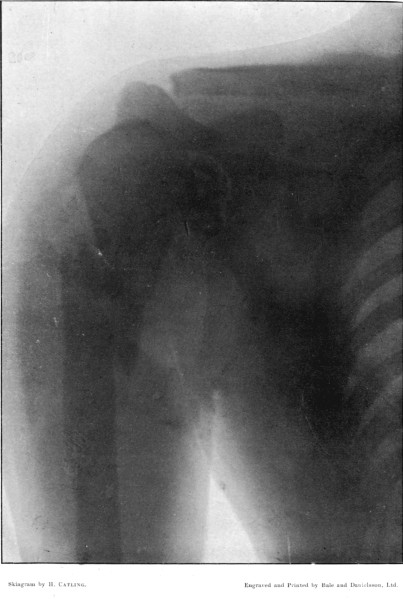

4. Comminuted Fracture of Shaft of Humerus180

5. Comminuted Fracture of Humerus accompanied by an Explosive Exit182

6. Comminuted Fracture of Humerus due to Oblique Impact184